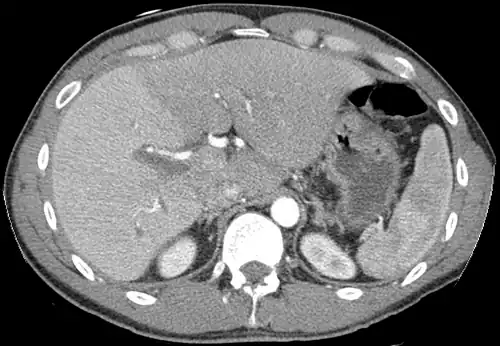

A CT scan in which the liver and portal vein are shown

With the recent advances of noninvasive imaging, living liver donors usually have to undergo imaging examinations for liver anatomy to decide if the anatomy is feasible for donation. The evaluation is usually performed by multidetector row computed tomography (MDCT) and magnetic resonance imaging (MRI). MDCT is good in vascular anatomy and volumetry. MRI is used for biliary tree anatomy. Donors with very unusual vascular anatomy, which makes them unsuitable for donation, could be screened out to avoid unnecessary operations.